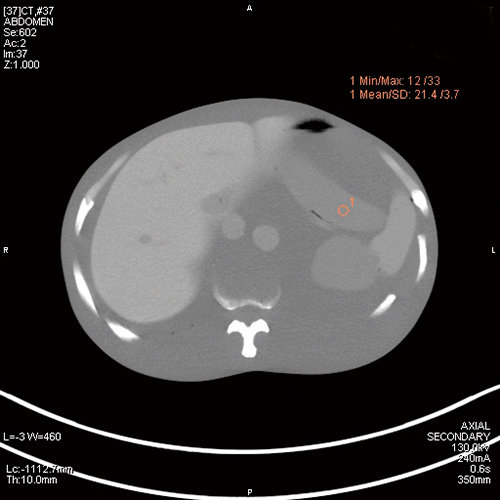

肝肿瘤